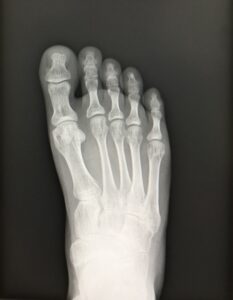

行軍骨折(第2,3中足骨疲労骨折)

行軍骨折は中足骨の疲労骨折で、下肢の疲労骨折のなかで脛骨に次いで多くみられます。“行軍骨折”という名称は、軍隊の長距離の行軍中に発症することが多かったことに由来しています。 スポーツ障害として生じることが多く、第2およ […]